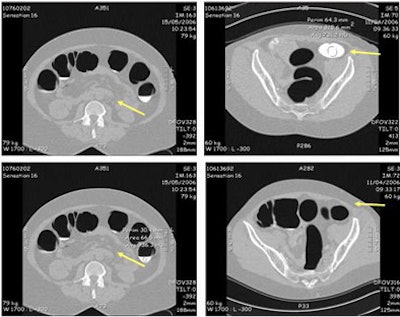

![]() |

| Residual fluid covered less than 20% of the colonic surface, and with prone and supine scanning, did not impair radiologists' ability to interpret data. Images courtesy of Dr. Didier Bielen. |

The imaging results showed "residual fluid covering less than 20% of the colonic surface," Bielen said. "This fluid was homogeneously tagged in the majority of patients: 72 of 75. Nine patients showed a high-density film covering parts of the colonic surface," he said. "Two patients showed rather inhomogeneously tagged fluid with a lower density of around 200 HU -- this was especially true in the right side of the colon."

Residual stool was present in varying amounts in most patients, and stool tagging was homogeneous in just two patients, Bielen said. Even so, the inhomogeneously tagged stool was relatively easy to distinguish from lesions by its texture, and as it changed position between supine and prone scanning.